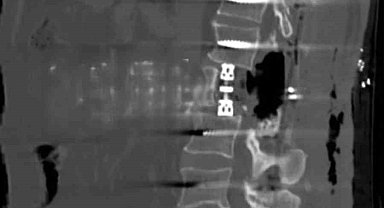

Bayburt'ta omur gövdesi çıkarılarak yapılan ameliyat başarıyla gerçekleşti